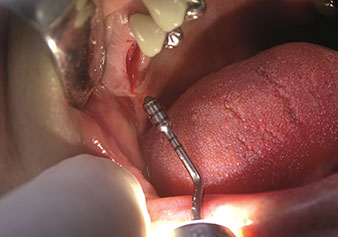

Situation post-extraction piézochirurgicale

Fig. 2 : Situation post-extraction piézochirurgicale. Photo : © Dr Torsten Conrad (Bingen am Rhein)